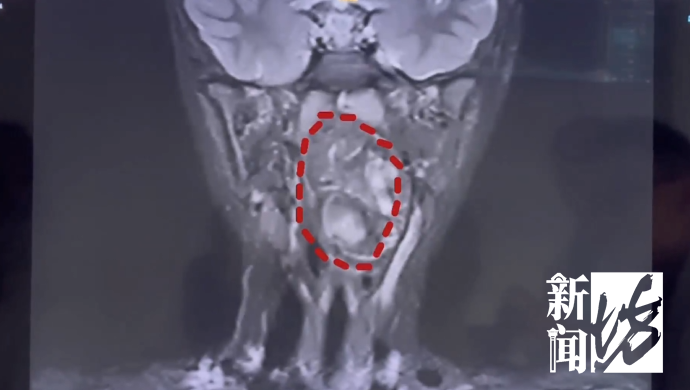

复旦大学附属儿科医院 耳鼻咽喉头颈外科副主任 陈超:我们可以看出它有脂肪,有软骨,这是一对双胞胎,一个是我们正常的人发育成的人,另外一个他可能残留在这个咽旁间隙里面,就发育成了这样的一个畸胎瘤。

医生解释,虽然畸胎瘤绝大多数是良性,但多生于腹腔内。像这样长在儿童咽喉部,而且又这么大的,极其罕见。肿瘤还在长大,如不及时干预,孩子恐有生命危险。

复旦大学附属儿科医院 耳鼻咽喉头颈外科副主任 陈超:6岁男孩的口咽腔大概在8公分左右,这个孩子的肿瘤已经高达6公分多,整个气道已经完全被这个膨大的肿瘤占据了,只有一条黑颜色的线,这是它透气的空间,再让它继续膨胀下来,它首先出现的一个症状应该是呼吸道的梗阻窒息,会出现窒息致死的可能。

雪上加霜的是,由于肿瘤紧贴颈内颈动脉,甚至明显将颈鞘压弯,手术的出血风险极高,这或许也是当地医院没有收治的原因。